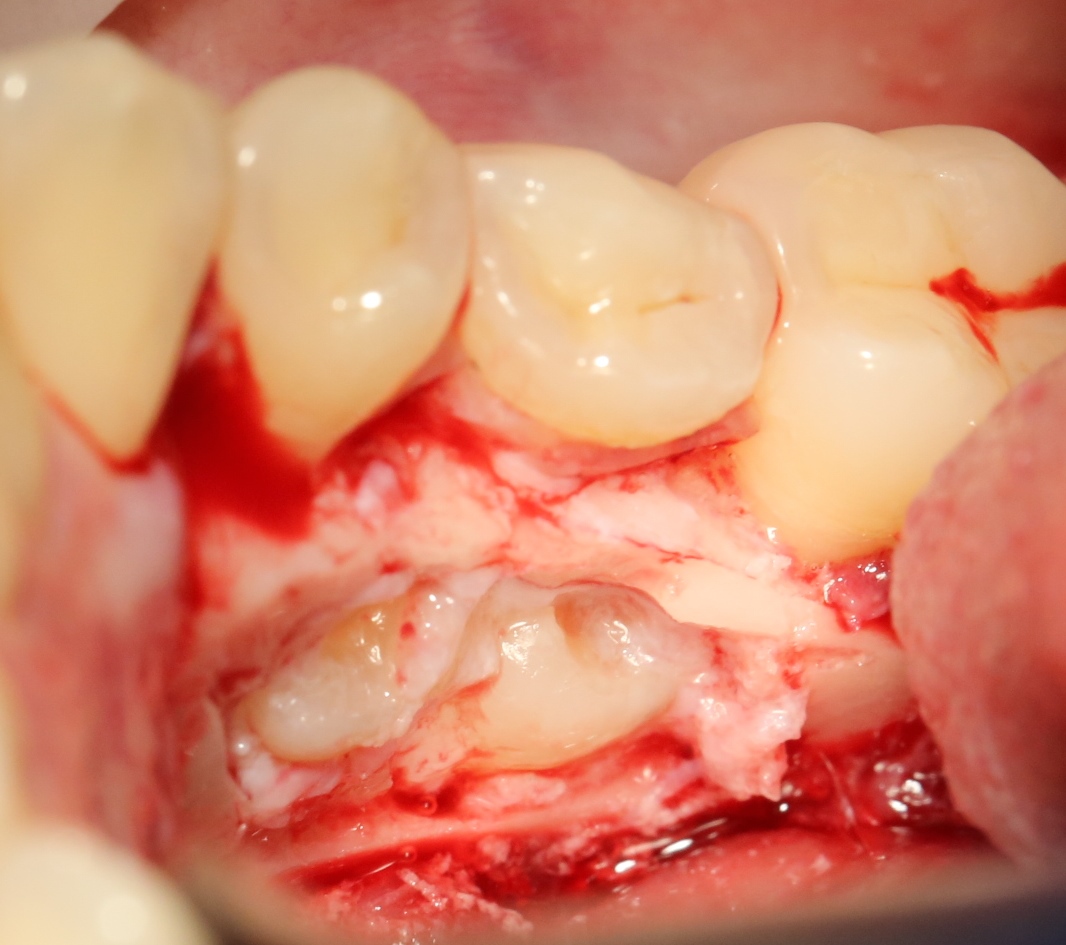

Итак, ультразвуковой разрез по костной ткани:

Костная «дверца» на время отделяется и убирается в физраствор, а мы видим следующее:

Это фолликулы и, частично, коронковые части сверхкомплектных зубов.

Теперь аккуратно нам нужно выделить сами зубы:

А вот они! Далее мы руководствуемся главным правилом хирурга-стоматолога:

Поэтому мы, всё также, с помощью ультразвука, отпиливаем коронку одного из зубов:

После чего, зубы вываливаются из лунок самостоятельно. В прямом смысле слова:

Вот удаленные зубы:

А вот их лунки:

Теоретически, лунки можно чем-нибудь заполнить. Только чем? И для чего?

Костная ткань сама регенерирует, если ей не мешать. Поэтому не стоит толкать в лунки какой-нибудь остеопластический материал, типа Cerabone или Bioss. Нет смысла.

В данном случае я использовал обычную коллагеновую губку — и то, только для того, чтобы «костная дверца», которую я выпилил в самом начале операции, не провалилась внутрь:

Теперь запиливаем «костную дверцу» на ее законное место:

И накладываем швы.